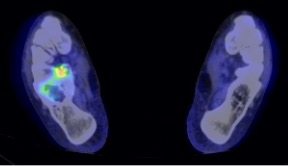

Pre-treatment PET-CT activity of giant cell tumour of the calcaneum showing marked peripheral FDG uptake

Post denosumab treatment PET-CT of the same lesion showing tumour response with reduced FDG uptake